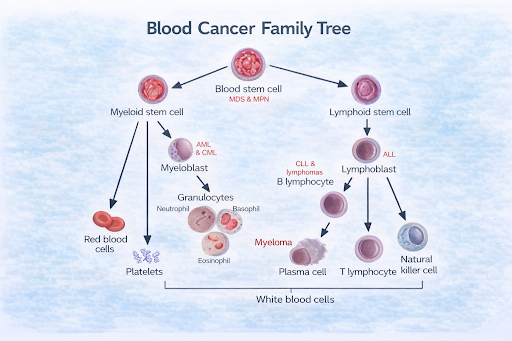

What are Blood Cancers and Lymphomas?

Blood cancers are a group of cancers that affect the blood, bone marrow, or lymphatic system. Lymphomas are a type of blood cancer that primarily involves the lymphatic system, which plays an important role in immunity. These cancers occur when certain blood-forming or immune cells begin to grow and behave abnormally.

Blood cancers are a group of cancers that affect the blood, bone marrow, or lymphatic system. Lymphomas are a type of blood cancer that primarily involves the lymphatic system, which plays an important role in immunity. These cancers occur when certain blood-forming or immune cells begin to grow and behave abnormally.

How does it develop?

These cancers typically develop when blood or immune cells undergo genetic changes that alter their growth and division. Instead of maturing normally, these cells may multiply uncontrollably and fail to function properly. Over time, they can crowd out healthy cells or interfere with normal immune responses.

Leukaemia: Types and Staging

Types of Leukaemia

Leukaemia is commonly grouped based on how quickly it develops and the type of blood cell involved.

Acute Leukaemia

Develops rapidly and involves immature blood cells. Symptoms often appear suddenly and require prompt medical attention.

Chronic Leukaemia

Develops more slowly and involves more mature blood cells. Some people may have few or no symptoms initially.

Leukaemia is also classified by the blood cell affected:

Staging of Leukaemia

Leukaemia is not staged like solid tumors. Instead, doctors assess:

Lymphoma: Types and Staging

Types of Lymphoma

There are two main types:

Hodgkin Lymphoma

Characterised by the presence of a specific abnormal cell type.

Non-Hodgkin Lymphoma

A larger group with many subtypes that vary in how they grow and respond to treatment.

Leukaemia: Types and Staging

Types of Leukaemia

Leukaemia is commonly grouped based on how quickly it develops and the type of blood cell involved.

Acute Leukaemia

Develops rapidly and involves immature blood cells. Symptoms often appear suddenly and require prompt medical attention.

Chronic Leukaemia

Develops more slowly and involves more mature blood cells. Some people may have few or no symptoms initially.

Leukaemia is also classified by the blood cell affected:

- Lymphocytic Leukaemia – affects lymphocytes

- Myeloid Leukaemia – affects myeloid cells

Staging of Leukaemia

Leukaemia is not staged like solid tumors. Instead, doctors assess:

- Blood and bone marrow test results

- The number of abnormal cells

- Effects on organs such as the lymph nodes, liver, or spleen

Lymphoma: Types and Staging

Types of Lymphoma

There are two main types:

Hodgkin Lymphoma

Characterised by the presence of a specific abnormal cell type.

Non-Hodgkin Lymphoma

A larger group with many subtypes that vary in how they grow and respond to treatment.